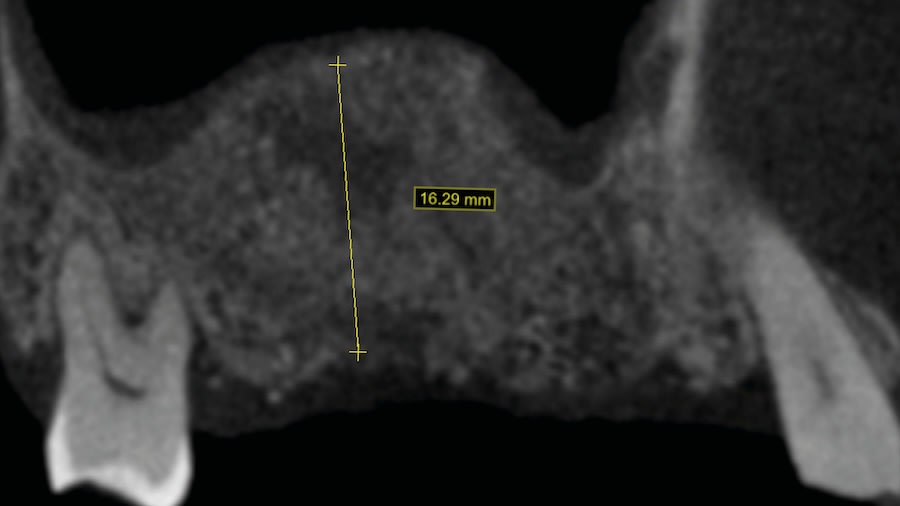

Case 1 (Figure 3 through Figure 24) depicts a 3-year follow-up of combined osseodensification sinus protocol IV in a severely resorbed maxillary ridge with ≤0.5 mm bone height in molar sites and horizontal deficiency at the first premolar site, using a two-stage approach for implant placement.

Step 1: Measure bone height at the osteotomy site on the CBCT. Measure ridge clinical width. A minimum of 7 mm alveolar ridge width is needed. Perform horizontal incision 2 mm to 3 mm palatally from the planned osteotomy site and elevate the flap using regular techniques of the clinician’s choice.